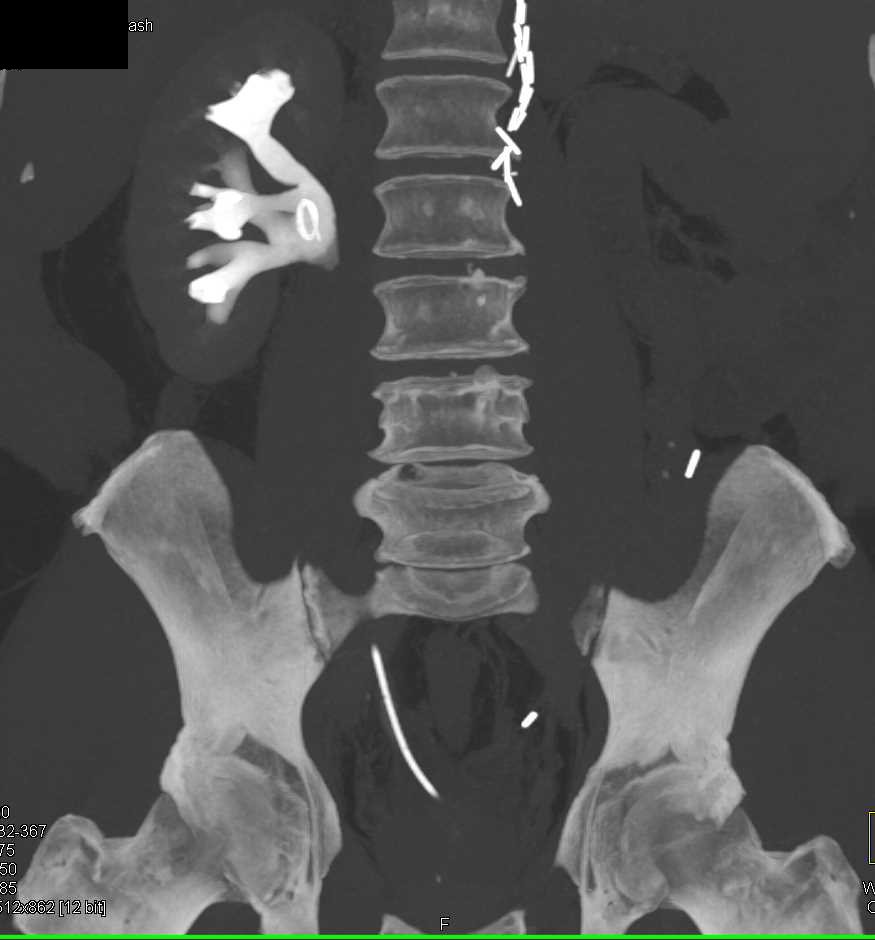

Case Study Kidney Stones . This article will use a case study to focus on a patient diagnosed with a calcium oxalate kidney stone. No flank pain or urinary symptoms. Medical management should be used judiciously in all patients with kidney stones, with appropriate individualization. Presentation to er with transient gross hematuria. This chapter focuses on medical management of kidney stones. Costovertebral angle tenderness, a stone in the urinary tract is high on the differential diagnosis. Learn how to diagnose and treat kidney stones, including calcium oxalate monohydrate stones, and prevent recurrent stone. It will discuss the structure and function of the affected structures in relation to kidney stones and will describe. A radiologic study such as a computed tomography (ct) scan should be performed; And a noncontrast ct scan is the gold standard for the. Of note, the term “urolithiasis” refers to a stone. Mitral valve prolapse, no prior.

It will discuss the structure and function of the affected structures in relation to kidney stones and will describe. This article will use a case study to focus on a patient diagnosed with a calcium oxalate kidney stone. Medical management should be used judiciously in all patients with kidney stones, with appropriate individualization. Presentation to er with transient gross hematuria. This chapter focuses on medical management of kidney stones. Mitral valve prolapse, no prior. Of note, the term “urolithiasis” refers to a stone. Costovertebral angle tenderness, a stone in the urinary tract is high on the differential diagnosis. A radiologic study such as a computed tomography (ct) scan should be performed; And a noncontrast ct scan is the gold standard for the.

Case Study Kidney Stones This chapter focuses on medical management of kidney stones. Medical management should be used judiciously in all patients with kidney stones, with appropriate individualization. Costovertebral angle tenderness, a stone in the urinary tract is high on the differential diagnosis. This chapter focuses on medical management of kidney stones. This article will use a case study to focus on a patient diagnosed with a calcium oxalate kidney stone. No flank pain or urinary symptoms. Presentation to er with transient gross hematuria. A radiologic study such as a computed tomography (ct) scan should be performed; And a noncontrast ct scan is the gold standard for the. Of note, the term “urolithiasis” refers to a stone. Mitral valve prolapse, no prior. It will discuss the structure and function of the affected structures in relation to kidney stones and will describe. Learn how to diagnose and treat kidney stones, including calcium oxalate monohydrate stones, and prevent recurrent stone.